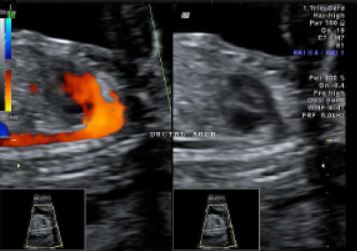

Fetal echo in rohini # available in delhi Fetal echocardiography, also known as a fetal echo, is an ultrasound test that examines the structure and function of an unborn baby's heart. It's usually performed during the second trimester of pregnancy